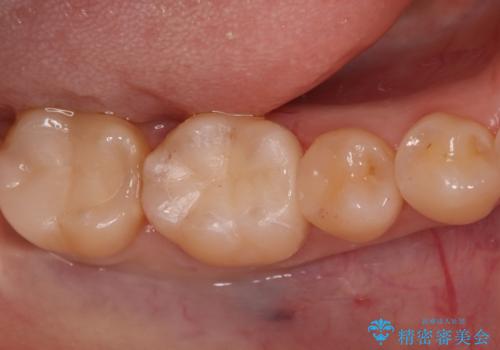

今回の治療では、まず左下6番と7番の欠損部に、骨の状態を考慮しながら慎重に2本のインプラントを埋入しました。インプラント体と骨がしっかりと結合するのを待った後、最短の期間で最終的な被せ物を装着するための精密な型取りを実施。最終的に、周囲の歯と調和した審美性の高いセラミック製の歯を装着しました。

治療期間は約3ヶ月で完了。以前の入れ歯のような煩わしさや動く心配がなくなり、天然歯と変わらない強い力でしっかりと食べ物を噛み砕けるようになり、快適な食生活を取り戻していただけました。